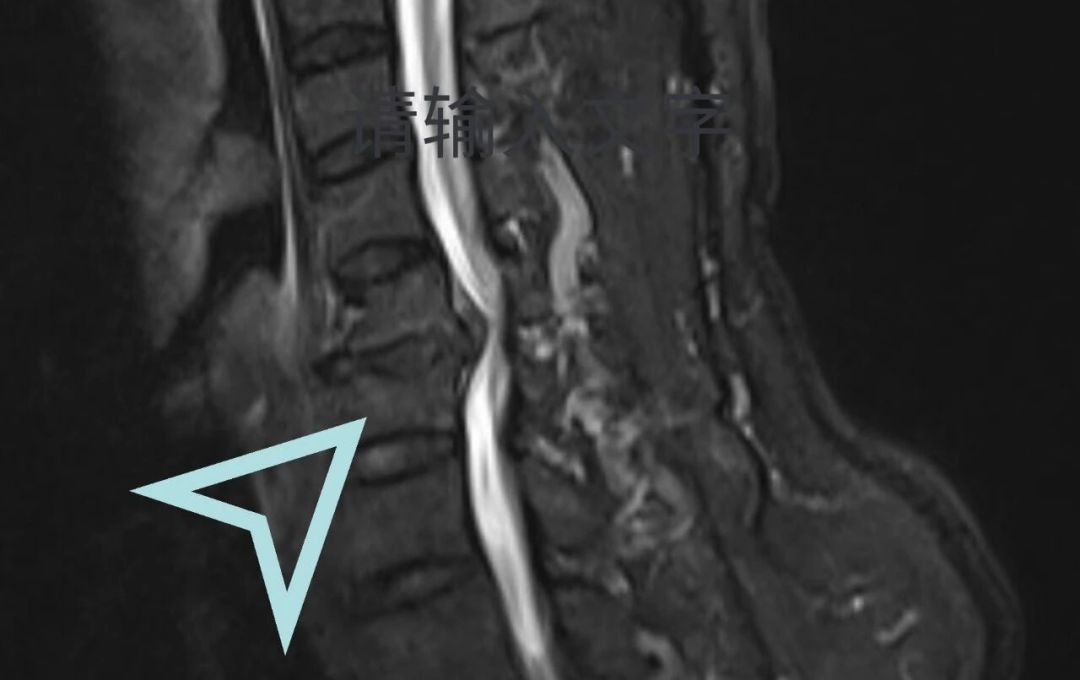

立即安排颈椎MRI检查让病灶“无所遁形”

检查结果实锤!李先生颈椎椎管狭窄、脊髓受压明显,确诊为脊髓型颈椎病——颈椎病里的“狠角色”!

马主任当即跟家属摊牌病情紧迫性:“保守治疗已无效,必须尽快手术!脊髓长期受压会造成不可逆损伤,轻微颈部磕碰都可能触发‘瘫痪预警’,拖不起!”

脊髓型颈椎病是颈椎病中最严重的类型之一,是由于颈椎退变导致椎间盘突出、骨赘增生、后纵韧带肥厚等压迫供应脊髓的血管,从而出现颈脊髓损害的颈椎疾病。其主要症状包括四肢麻木、无力,以及大小便功能障碍等。脊髓型颈椎病好发于中老年人,且男性居多,因保守治疗效果差,常需要手术治疗。